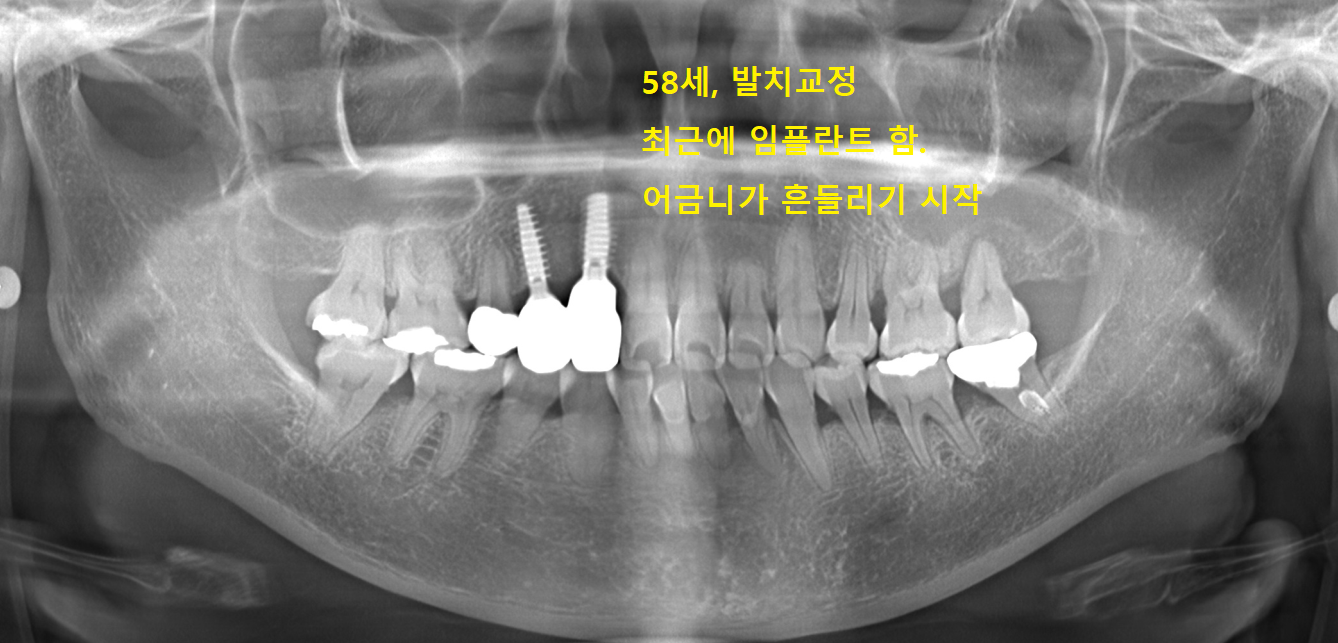

치아가 불규칙해서 청년기에 발치교정 받음,

덧니였던 송곳니를 뽑고 브릿지를 제작하면서 교정을 마무리함.

58세에 브릿지가 흔들려서 임플란트를 함.

이어서 어금니가 흔들리는 것을 느낌.

시간 간격을 두고 어금니들이 발치될 것으로 보임.